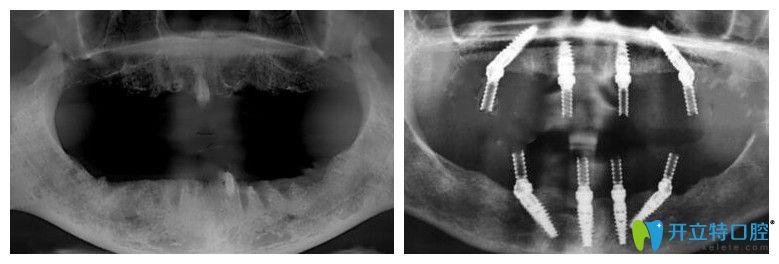

65歲,薛老師;種植前上頜牙齒全部脫落,下頜就剩下四顆殘根;之前戴過活動假牙,但因為時間長了戴上很容易掉,所以才考慮做全口種植牙。下面是做種植牙前后的CT片:

薛老師說沒做種植牙前聽別人說價格特別貴,但是在靖江艾齒嘉口腔面診、拍片檢查后,陳濤醫(yī)生建議自己做ALL-ON-4全口種植牙,上下頜各植入4顆種植體,就能支撐全口牙冠,這種方法不僅讓自己省了很多錢,而且吃東西的咀嚼力也強。